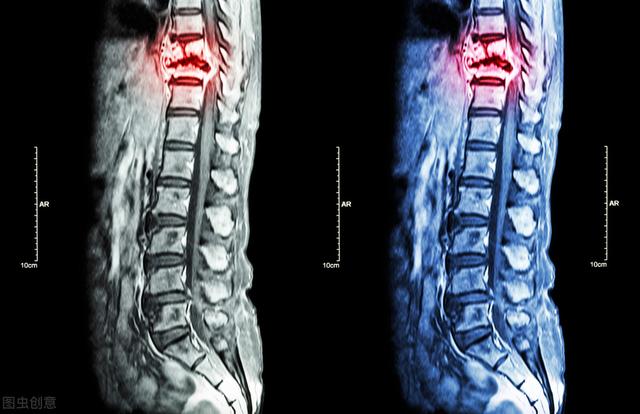

骨転移の磁気共鳴画像法

がんによる骨転移患者の痛みには一定の特徴がありますが、一般的な病気と干渉する症状も見受けられます。もし患者が発生した場合、脊椎の骨転移が神経を刺激し、医師や患者が椎間板ヘルニアによって誘発された症状を誤診しやすく、この時、患者として、体に異常があるため、適時に医師の助けを求め、医師として患者とコミュニケーションを図り、比較的質の高い検査を行い、骨転移のリスクを除外しようとする。例えば、高齢者の長期的な腰痛に対しては、レントゲン検査の代わりにMRI検査を行うことをよく勧める。例えば、慢性的な腰痛を持つ高齢者に対しては、レントゲン検査の代わりにMRI(磁気共鳴画像装置)検査を受けるよう勧めることがよくあります。

がんの既往があり、その時点で悪性度が高いと判断されれば、全身骨シンチで骨転移の有無を調べることができる。同時に、転移部位の骨破壊の程度を磁気共鳴検査で明らかにすることができる。